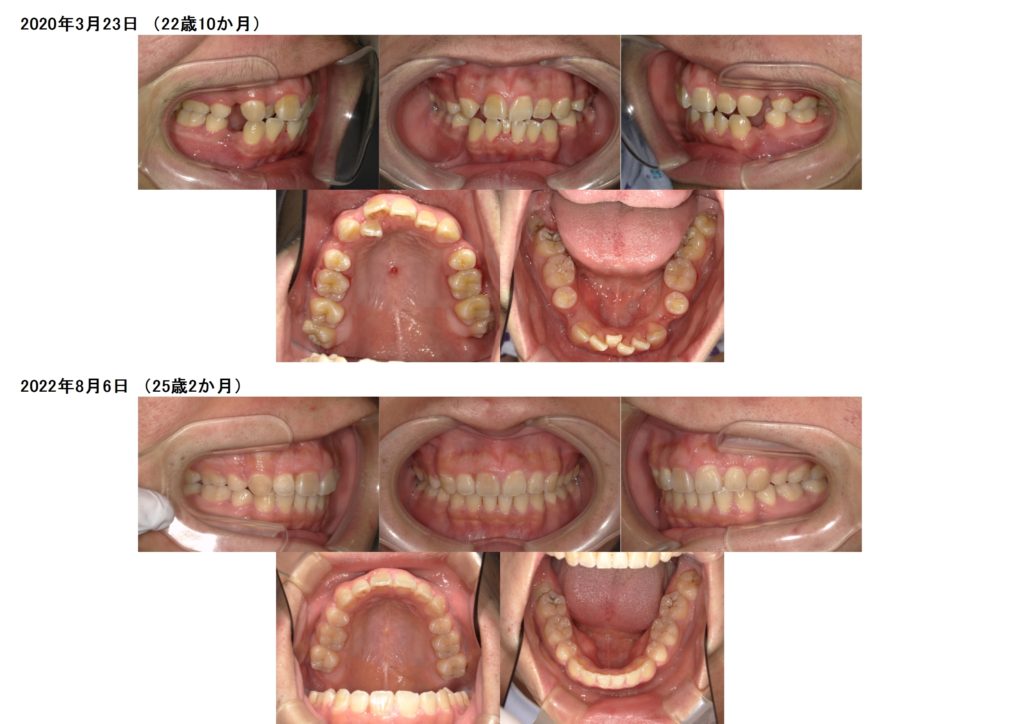

今回は マウスピースを使用し上下抜歯の治療例です。

この患者様は上下4番目の歯を抜歯してマウスピースにて治療をしました。

とってもキレイになりましたよね☺

途中、マウスピースをの作り直しをしながら、しっかりと真面目に使って頂けて、治療が終われました!!